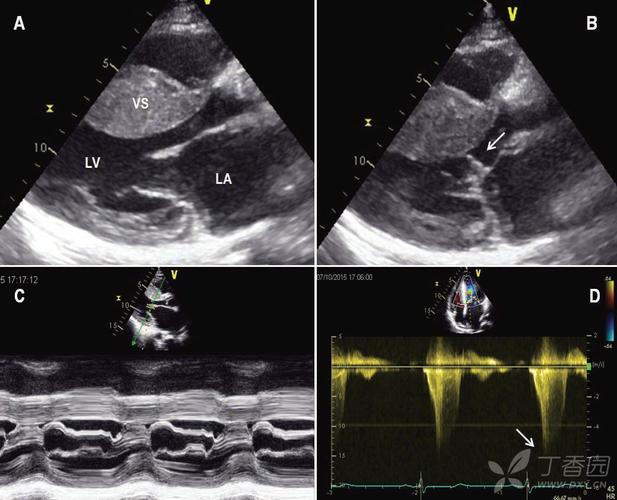

sam征超声表现,sam征

网易首页>正文申请入驻> 选自《心血管超声诊断学图解》赵博文主编

超声心动图 sam征小知识

二尖瓣可见偏心性返流,提示该患者存在sam征

实际上这幅超声图像采集自一例安装有左心室辅助装置的心衰终末期患者

sam征

二尖瓣sam征示意图

二尖瓣sam征图

sam征超声示意图

sam征超声心动图

sam现象超声图片

sam征阳性超声图片

二尖瓣sam征M型示意图

肥厚型心肌病sam征图片